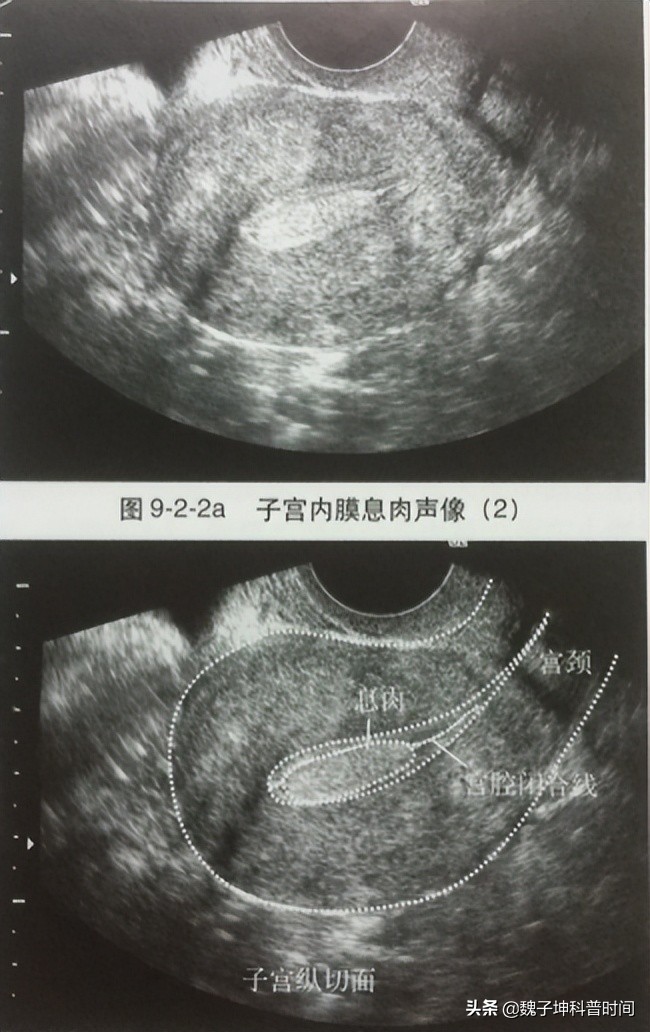

所谓宫腔镜检查,通俗理解就是通过一条细小镜子伸入到宫腔内观察病变的诊断方法。与超声和核磁共振检查相比,其优势就是直接走进了宫腔内进行观察,所获信息由猜测变为确定、由模糊变为清晰、具体,优势无可替代。我们来看一组对比,图1为B超下的子宫内膜息肉,图2为宫腔镜下的子宫内膜息肉,即使不学医的朋友也能看出来宫腔内长了多余的东西。